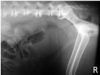

What is shown in these images?

A

normal prostate in an intact dog

-arrow heads indicate the prostate

-white line represents distance between sacral promontory and pubis